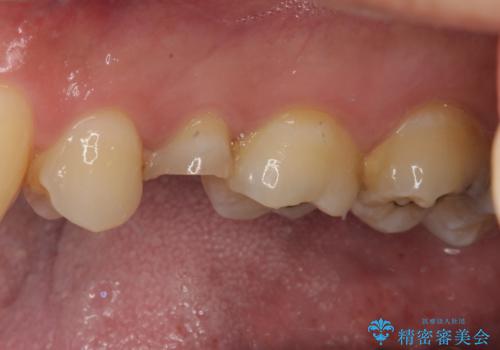

補綴治療後3ヶ月での経過は良好で、引き続き経過観察を行っていきます。